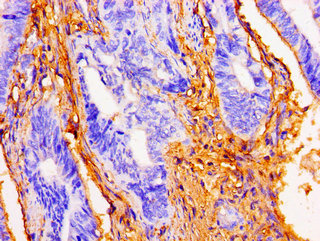

Immunohistochemistry of paraffin-embedded human colon cancer using CSB-PA861938LA01HU at dilution of 1:100